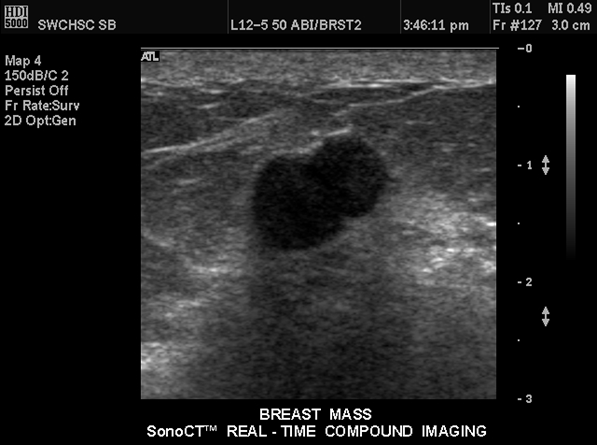

What are theses images showing?

fibroadenoma on ultrasound